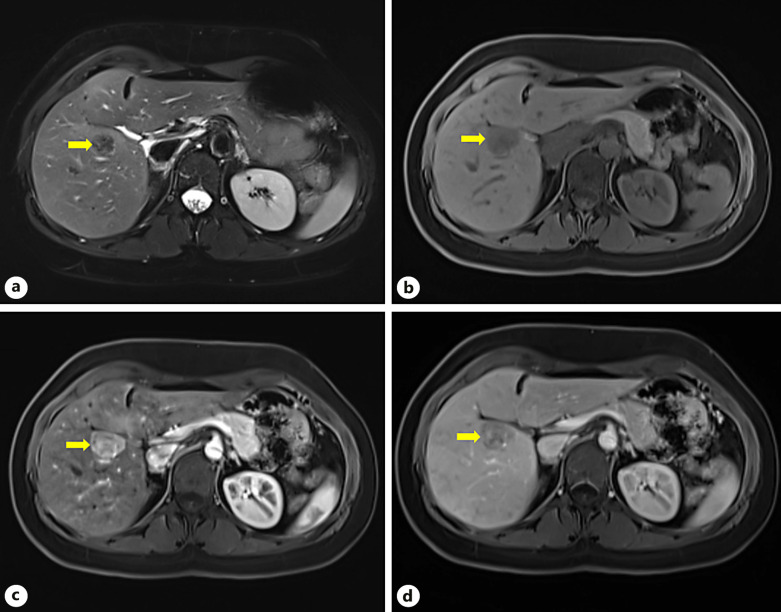

Case presentation: We present a case report of a 33-year-old female patient with a history of macroprolactinoma. She was initially referred to our Department due to a 9-mm hepatic nodule incidentally diagnosed in an abdominal ultrasound in 2018. She was asymptomatic. Follow-up ultrasound showed a growth from 9 mm to 16 mm in 2019 and 30 mm in a liver magnetic resonance imaging (MRI) scan in 2022. The case was discussed in a multidisciplinary team meeting, and since malignant transformation or hepatocellular carcinoma could not be ruled out, the decision was to undergo hepatic resection. An open hepatic subsegmentectomy of segment 5 was performed, with uneventful postoperative period. The definitive diagnosis was hepatic PEComa.

Conclusion: Hepatic PEComas are rare liver tumors, and their preoperative diagnosis is challenging due to the lack of specific radiological features. In most cases, the diagnosis is only confirmed through histopathological and immunohistochemical studies. Resection of the lesion appears to be the curative treatment; however, due to the rarity of the condition, there are no studies comparing surgical treatment with other options. In our case, the hypervascular lesion was initially misdiagnosed as an adenoma. PEComas should be considered as a differential diagnosis in liver nodules with well-defined margins and increased uptake in the arterial phase in computed tomography or MRI scan. Surgical resection was curative, and no recurrence was detected during the patient's follow-up.